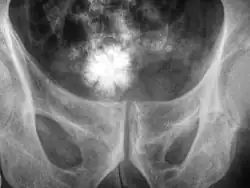

Jackstone calculus

Jackstone calculi are rare bladder stones that have an appearance resembling toy jacks. They are almost always composed of calcium oxalate dihydrate and consist of a dense central core and radiating spicules. They are typically light brown with dark patches and are usually formed in the urinary bladder and rarely in the upper urinary tract. Their appearance on plain radiographs and computed tomography in human patients is usually easily recognizable. Jackstones often must be removed via cystolithotomy.[10]